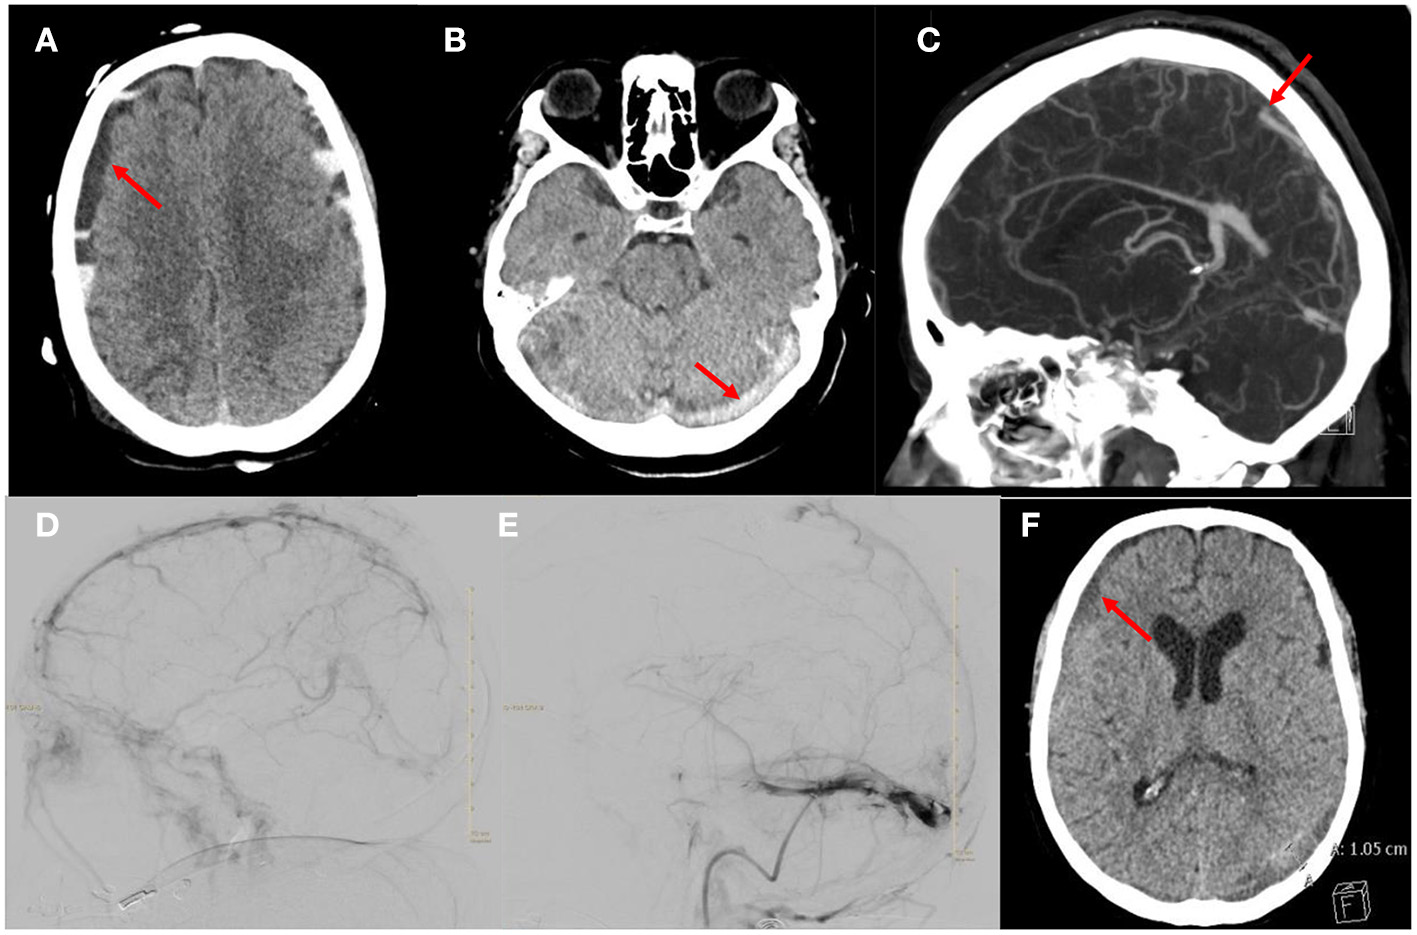

A 69-year-old female presented with COVID-19 pneumonia, altered mental status, atrial fibrillation with rapid ventricular response and severe diarrhea. A head computed tomography (CT) was obtained which showed the initial mixed density acute subdural hematoma (Figure 1A). An additional axial head CT demonstrated multifocal hyperdensities throughout the dural sinuses, highly concerning for multifocal acute dural sinus thrombosis (Figure 1B). She was admitted to the medical intensive care unit (MICU) COVID unit, resuscitated and started on a heparin infusion. Her neurologic course was also complicated by status epilepticus which required intubation, burst suppression and multiple anti-epileptics agents. A CT venogram (CTV) was obtained which confirmed the diagnosis of multi-focal sinus thrombosis. Occlusions were identified in the superior sagittal sinus (SSS), torcula, bilateral transverse sinuses/sigmoid to the jugular bulb and straight sinus along with generalized venous congestion (Figure 1C). While in burst suppression a surveillance head CT was obtained which demonstrated interval development of bilateral hemispheric and posterior fossa mixed density subdural hematomas and generalized sulcus effacement. An optic nerve sheath diameter was obtained, which measured 6 mm, suggestive of intracranial hypertension. The heparin infusion was paused briefly until a definitive treatment plan could be developed.

Figure 1

Images from the patient who received mechanical thrombectomy and anticoagulation for aSDH with CVST. (A) Axial head CT demonstrating the mixed density acute subdural hematoma. (B) Axial head CT demonstrating hyperdensity in the torcula and transverse sinuses suggestive of acute thrombosis. (C) Sagittal CTV demonstrating occlusion of the SSS, straight sinus and torcula along with generalized venous congestion. (D) Right ICA injection, lateral projection of late venous phase demonstrating thrombus in the SSS and partial occlusion of the straight sinus and occlusion of the transverse sinuses. (E) Venogram of right sigmoid sinus, lateral projection after thrombectomy and tPA infusion showing improvement in drainage of the SSS and transverse sinus. Note there is a persistent non-occlusive thrombus of the transverse sinus. (F) Axial head CT demonstrating decreased size of the subdural hematoma.

A multi-disciplinary team discussed multiple treatment options, and ultimately decided with family to resume therapeutic anticoagulation and proceed with endovascular mechanical thrombectomy of the venous sinuses. She was taken for mechanical thrombectomy of SSS and transverse sinuses thrombus with thrombo-aspiration and stent-retriever techniques. Three thrombectomy passes were made using the Solumbra technique with a Trevo 4 × 40 mm stent retriever device, polyvinyl alcohol particles 150–250 microns, and an aspiration catheter. After the third pass, she developed acute desaturations which were concerning for clot mobilization and a pulmonary embolism. The microcatheter was left in the SSS and recombinant tissue plasminogen activator (tPA) was infused for 10 h. The patient's respiratory status quickly improved but several hours after the procedure she developed anisocoria. A head CT was obtained which demonstrated interval expansion of the hemispheric mixed density SDH, global effacement of the sulci and 4th ventricle. The tPA infusion was discontinued. A decision was made to return to the endovascular suite for further attempts at thrombectomy. A total of five thrombectomy passes were completed with removal of large thrombus fragments after each pass.

The final angiogram showed significant improvement in antegrade venous drainage in the SSS, bilateral transverse and sigmoid sinuses with residual multifocal non-occlusive thrombi (Figures 1D,E). After a prolonged hospital course she was discharged to a long term acute care facility. On clinic follow up 10 months later, she had returned living at home independently with a modified ranking score of 2. A head CT obtained during the clinic follow up showed near complete resolution of the SDH (Figure 1F).